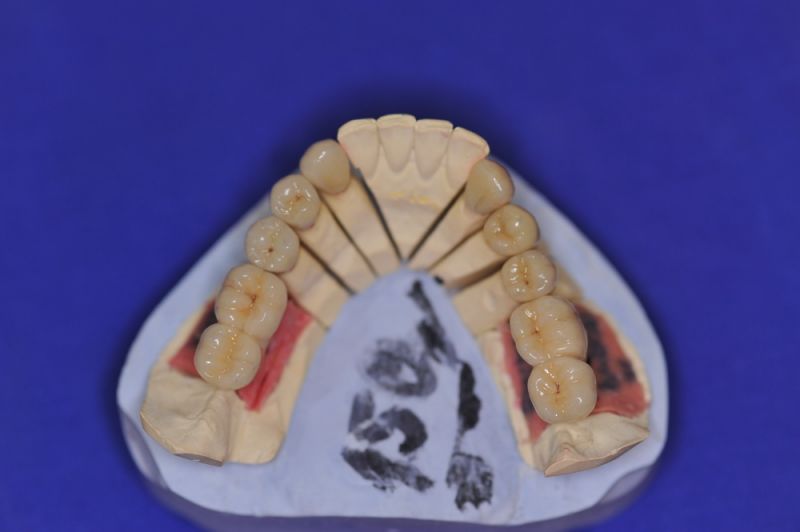

Mit dem heutigen Tag geht eine der technisch schwierigsten und anspruchsvollsten Arbeiten zu Ende, die im CMD-CENTRUM-KIEL jemals erstellt worden ist. Dabei sind es nur 10 Kronen, die benötigt werden, um die starken Kopf- und Gesichtsschmerzen der Patienten zu beseitigen.

4. Notwendigkeit die Mundhygienefähigkeit der Arbeit auch unter sehr beengten Verhältnissen zu schaffen, um der Arbeit eine günstige Prognose mitzugeben.